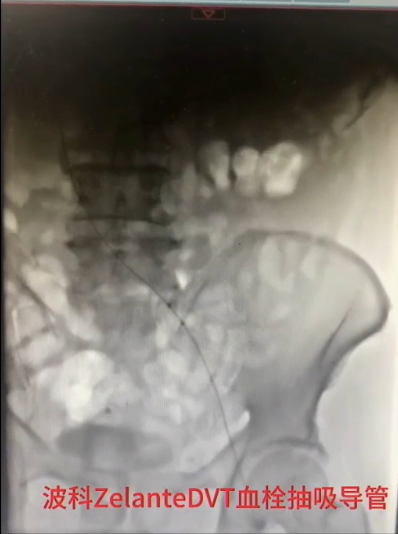

手术过程(三):导丝通过髂总静脉略有阻力,交换stiff导丝后,引入DVT血栓抽吸导管,连接AngioJet血栓抽吸装置,于髂股静脉处喷射配置好的20万IU尿激酶,20分钟后,再次引入导管,改为抽吸模式,在髂股静脉血栓内抽吸,部分团块较大的血栓往返抽吸数次。